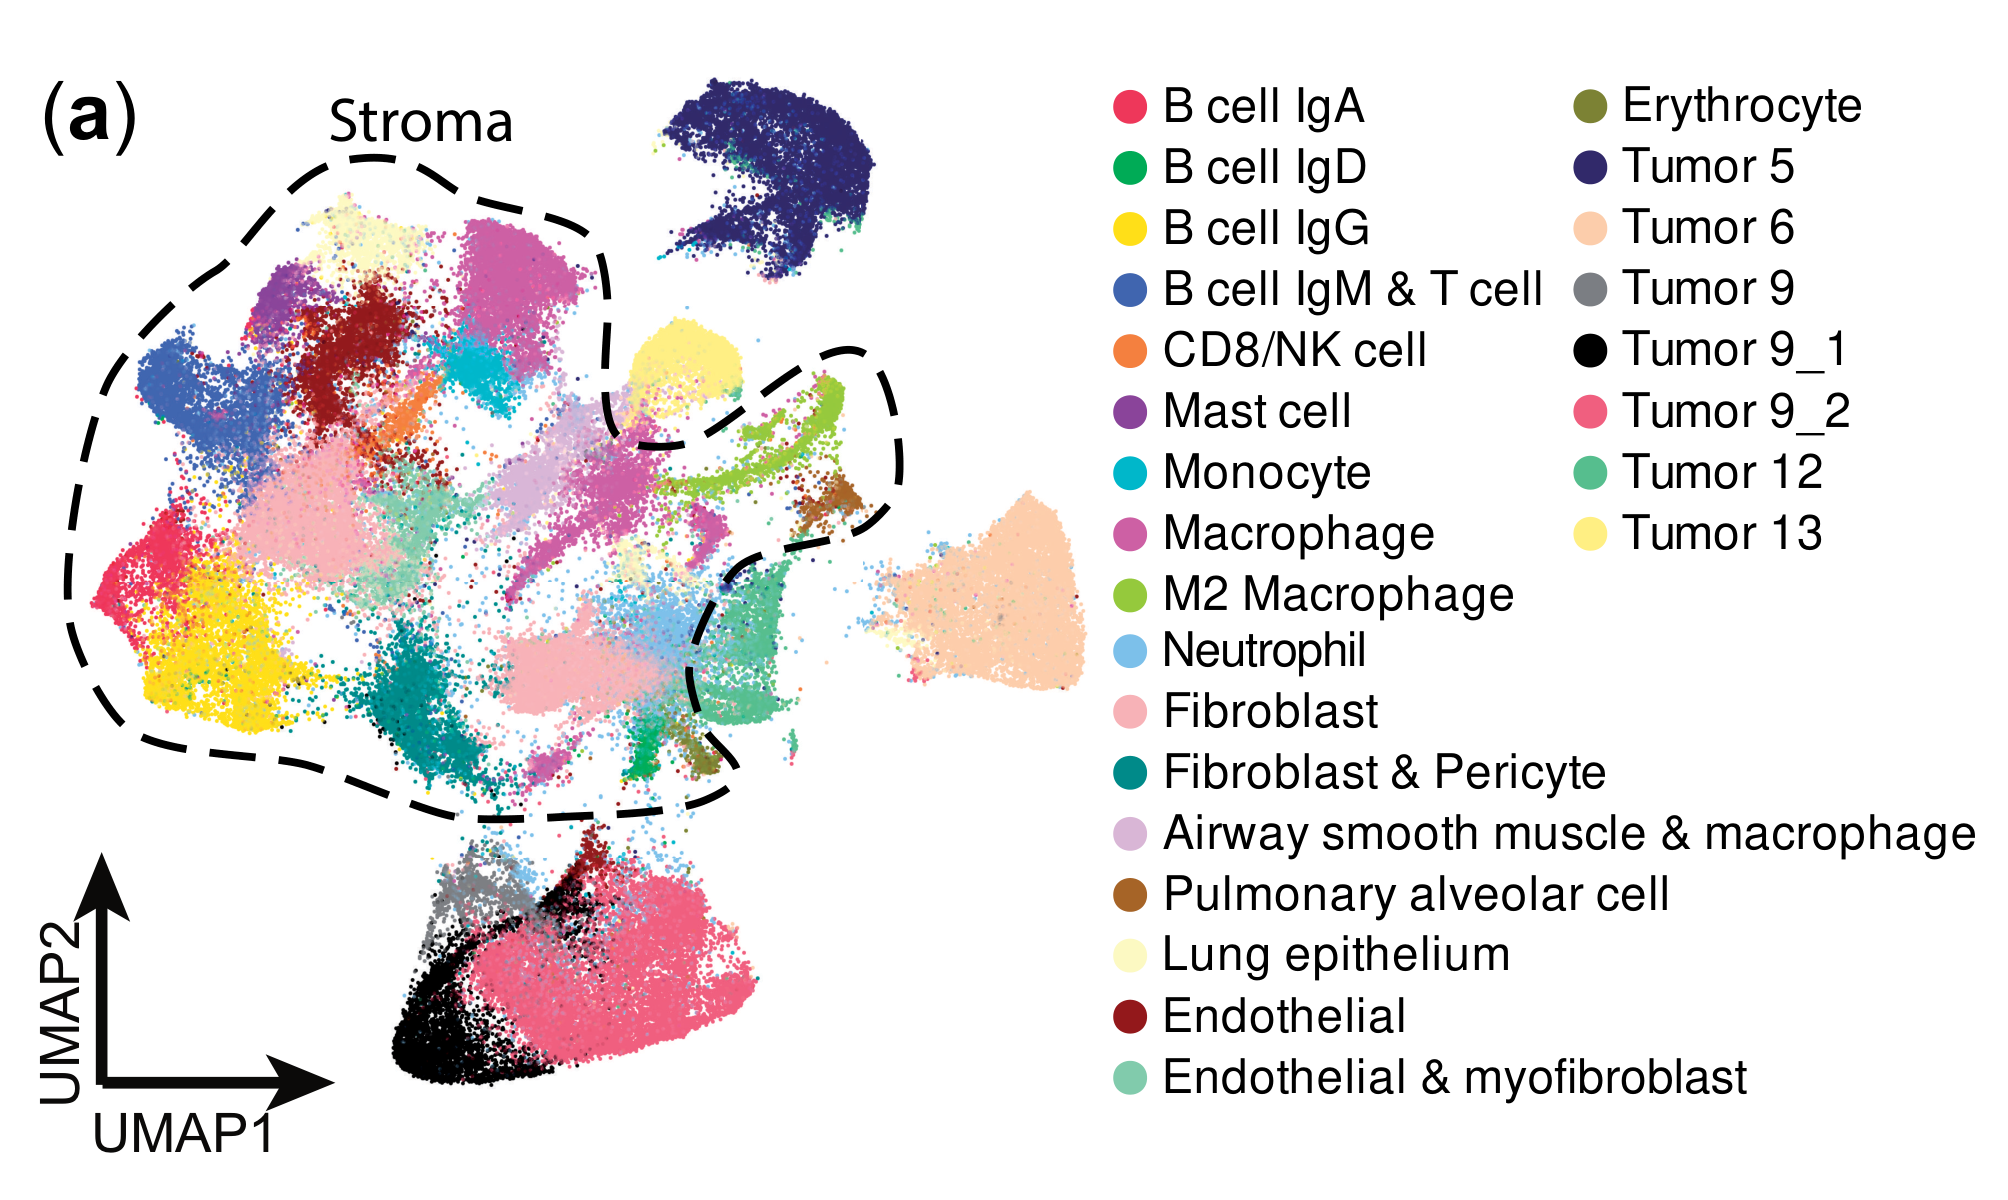

Allam et al., 2021

Spatially visualized single-cell pathology of highly multiplexed protein profiles in health and disease

Condition Dimension

Categorical

Data

Modality

Imaging-based

Resolution of observation

Cellular

Visualized Elements

ObservationRelationshipStatistic

Biological

MolecularSystemic/IntegrativeTissue

Abstraction

NonePartial

Chart Type

Dot ChartFlourescence tissue imageScatterplot

Communicative/Contextualization

AnnotationHighlighting

Comparative Design

Explicit encodingJuxtaposition

Layout

LinearSpatial : Physical

Scalability Strategy

Sampling/Filtering

What is the spatial localization and expression correlation between markers in both healthy and diseased tissues?